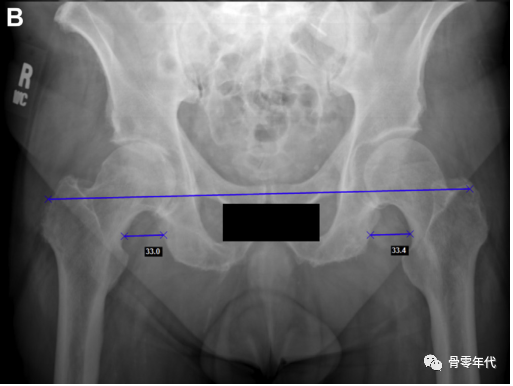

首先,在泪滴的水平线上画一条水平线。肢体长度从这条水平线测量到双侧小粗隆中心的水平。在小粗隆上选择了一个两侧看起来相等的位置。测量从颈部切口水平到坐骨的偏移量

然后画一条水平线连接两个泪滴的最下面的边缘。对于肢体长度,在小转子上选择一个双侧等效的点,并垂直于水平连接(图A)。为了确定偏移量,然后在每个股骨颈上选择一个点,大约在预期的颈部切口水平。从颈部这一点开始画一条线,平行于泪滴间线到坐骨边缘(图B)。

(A)内收和内旋对右髋关节偏移量的影响。与左侧臀部相比,这会产生一种减少偏移量的感觉。(B)骨盆倾斜对肢体长度和偏移量的影响,通过减小髋关节抬高时的偏移量和肢体长度,而对向下旋转的髋关节产生相反的影响。